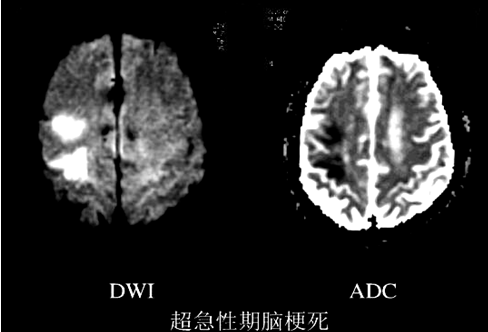

①超早期脑梗死的诊断

①脑脓肿:脓腔于DWI呈均匀高信号,ADC低信号--弥散受限,与脓液的高粘滞度和脓肿的多细胞性有关。